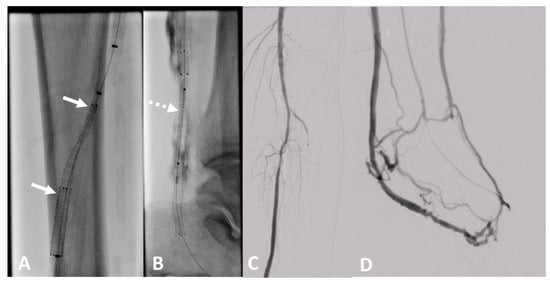

In recent years, pDVA emerged as a novel treatment option for CLTI patients without an option for conventional angioplasty or bypass caused by an absence of pedal vessels as a target for recanalization. For this procedure, long stent grafts are needed to redirect the arterial blood to the venous vessels of the foot to establish pressurization of the existing small venous vessels of the foot with oxygen-rich blood. The LimFlow stent grafts are dedicated to this indication [30] (Figure 11). However, the long-term experience with regard to patency is currently limited [31].

Figure 11. Clinical example of a patient treated at University Hospital Tuebingen with percutaneous deep venous arterialization (pDVA). The aim of this intervention is the redistribution of arterial blood to the foot via the tibial veins as a conduit. (A) Implantation of a dedicated tapered LimFlow endograft for crossing from the posterior tibial artery to a tibial vein (white arrows). (B) Straight LimFlow endografts in the tibial vein covering side branches until the foot (dotted arrow). (C) Angiographic of the proximal lower leg image after implantation of the LimFlow endografts. (D) Final angiographic result of the arterialized venous foot arch after successful pDVA.